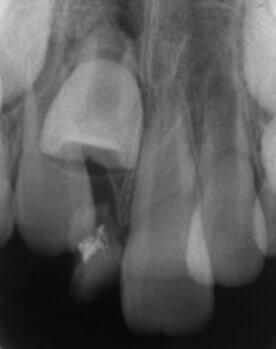

歯の外傷(転んだり、ぶつけたりして歯が欠けてしまった、抜けてしまった)